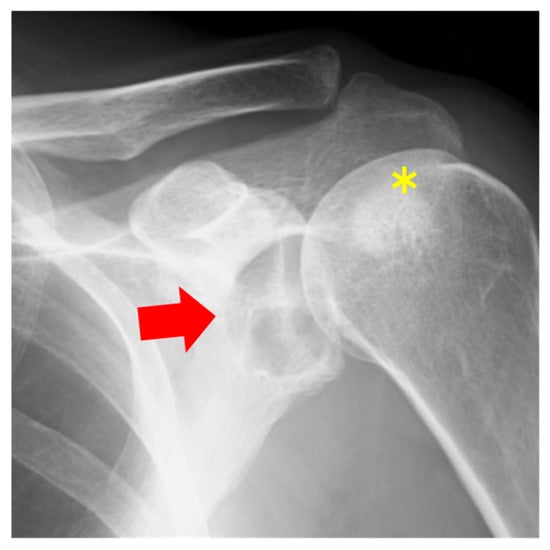

2.2. Case 2